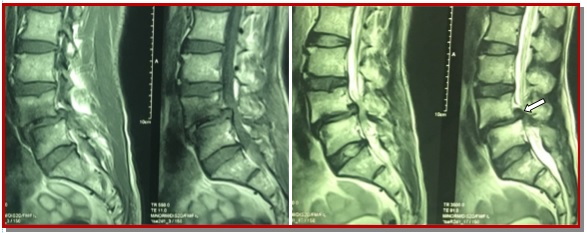

Spondylolisthesis is forward slipping of upper vertebra in relations to its lower one, commonest is L4-L5. The ideal surgical treatment of spondylolisthesis is still controversial. Posterior lumber interbody fusion with pedicle fixation is one of treatment choices for the lumber spondylolisthesis. Forty patients who operated through posterior lumber interbody fusion and pedicle screw fixation by single surgeon was included from January 2012 to March 2015. Periodical follow-up was done both clinically and radiologically up to 6 months. Patient outcome was completed based on pain relief graphic rating scale and Oswestry disability index. In our series, the excellent outcome were 25 patients (62.5%), good were 12 patients (30%), and fair were 3 patients (7.5%). There were no poor outcome and no new neurological deficit. This study concludes that posterior lumber inter-body fusion with pedicle is an effective treatment for the lumber spondylolisthesis. It helps to maintain the biomechanics, associated with less complication and improve the quality of life of patient.